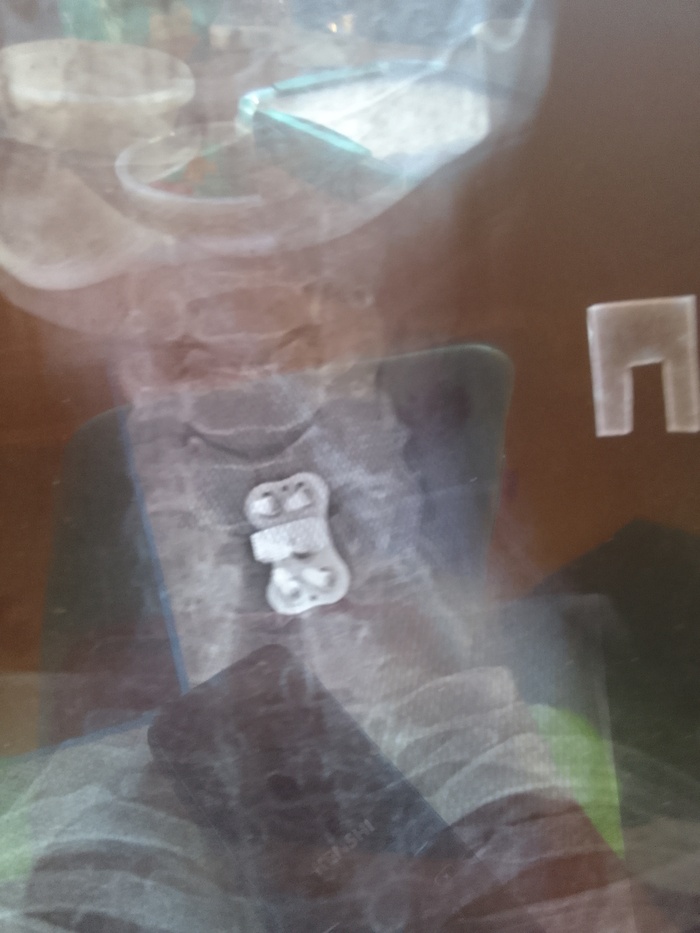

Всем привет. В общем и целом попал в дтп 24.09. (Мой апм совет не ездить на попутках). Собрали 4 встречных автомобиля,в 5-ю прилетел аккумулятор от нас.и разбил лобовое. Удар был в левый борт. Спасатели спилили крышу чтобы нас вытащить. Был за водителем слева. Сломано: шея, ключица, 3 ребра. Сотрясение мозга. 4 ушиба спинного мозга(позвоночника). Сидел я На пассажирском сиденье.был пристегнут. После аварии сделали 2 операции. 1. Вставили титановый межпозвонковый диск. 2 поставили плиту на левую ключицу из медицинской стали. Первую операцию делали через разрез на шее.по этому 1 месяц ел только детские пюре. Интервал между операциями 6 дней. Врачи сказали что Во время столкновения когда сломало шею, задело артерию. И кровью залило левое полушарие. В итоге была амнезия.сейчас все норм. Восстановился. Когла я окреп и воосстановился через 7 месяцев после дтп. Жена ушла от меня. Через 9 месяцев мы официально развелись по обоюдному согласию . С ней мы прожили без 3-х месяцев 10 лет. После развода. Прожили еще 10 дней. Она дала мне второй шанс. Но я неисправим. В итоге мы разошлись навсегда.живем сейчас по разным городам . Расстояние 3500 километров. Жизнь продолжается в новом ключе. У меня новая работа. Новая жизнь. Теперь живу один. Берегите себя и свою жизнь и цените то , что имеете. здоровье восстановилось все, кроме мозга. Алкоголь теперь под запретом. От слова совсем. Один раз попробовал . На утро 40 минут пытался вспомнить . Кто я и где я. Всем удачи в этой жизни и никогда не расстраивайтесь по пустякам. Я выжил. И я благодарен врачам за то что спасли. И жене(теперь уже бывшей) что выходила меня после аварии.